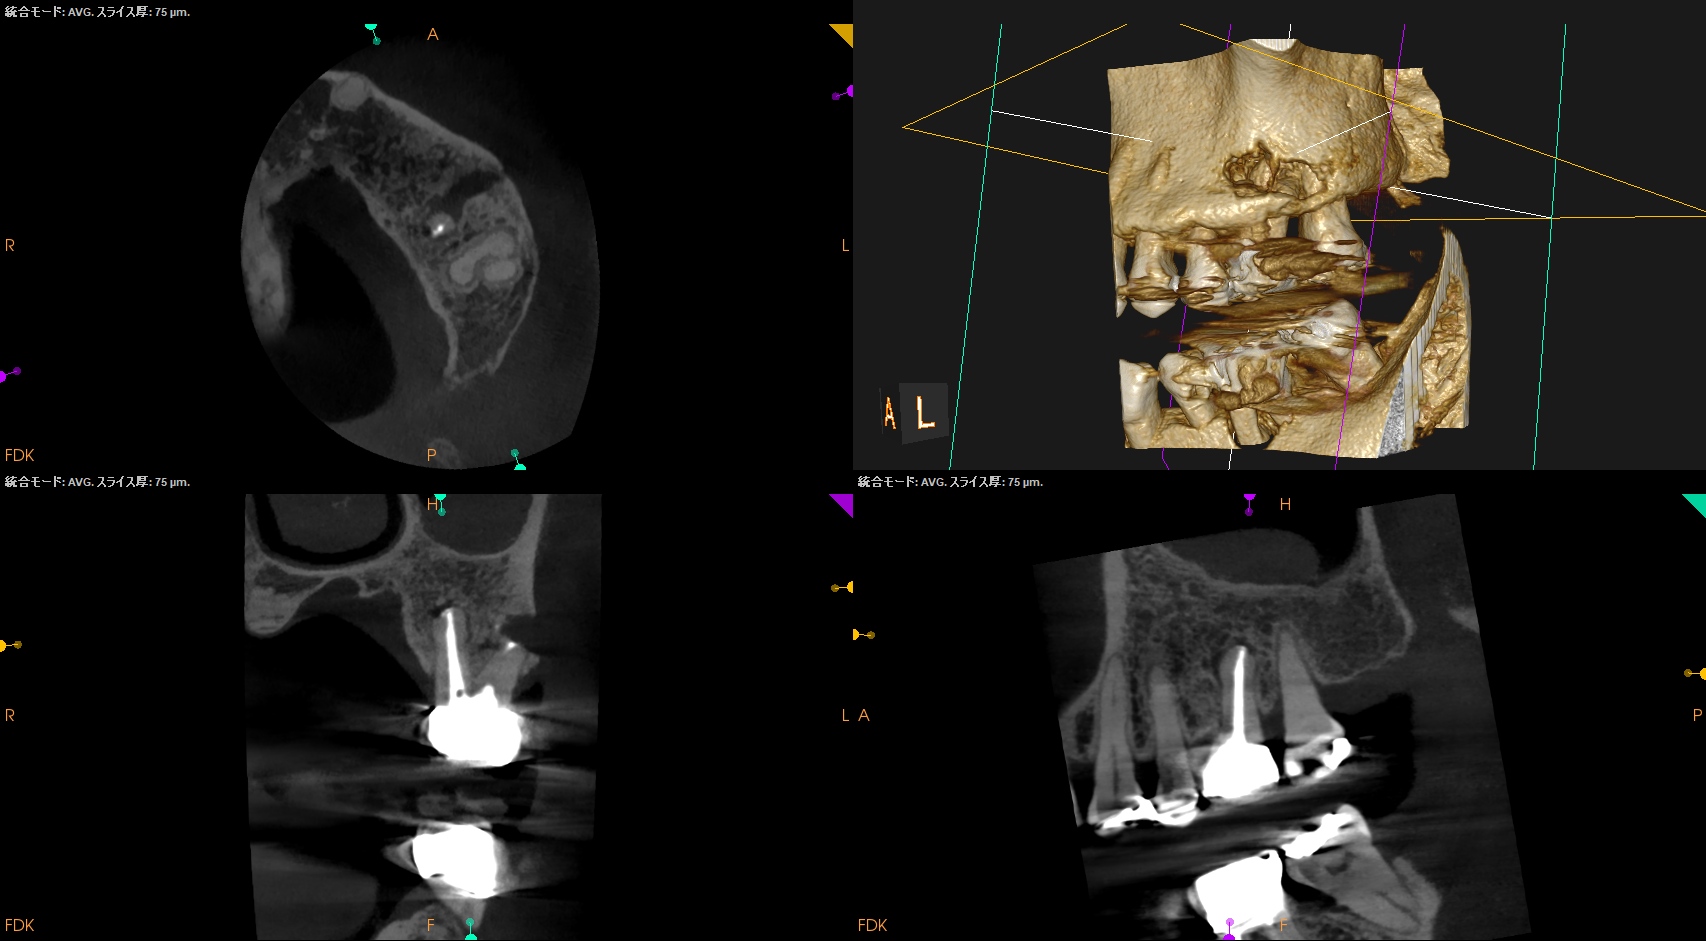

DBは楽だが、MBは頬舌径が7.4mmでMB1, MB2があるという…難ケースだ。

#14 MB,DB Apicoectomy(2026.2.12)

逆根充後にPA, CBCTを撮影した。